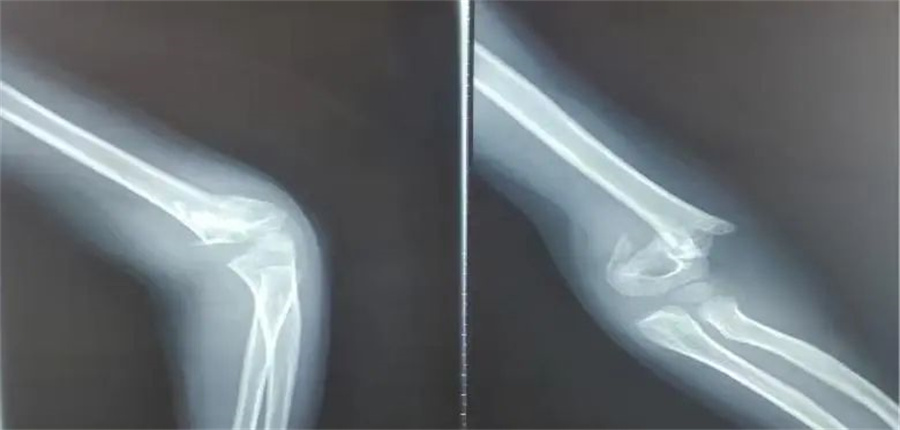

诚瑞的家长赶紧带他来到北京儿童医院集团医院·蜜桃视频 。入院当天,骨科医生发现,孩子是重度伸直型三度肱骨髁上骨折。

在各项检查指标都正常的情况下,儿童医院骨科的医护人员为他做了髁上骨折闭合复位术。

正常情况下,这属于常规手术。但是由于诚瑞太胖,胳膊又短又粗,复位的时候摸不到骨头,无形中增加了手术难度。

骨科医生在放射线下,一点一点摸索,最终复位成功,并且术后没有切口,没有瘢痕,4天后,孩子顺利出院。